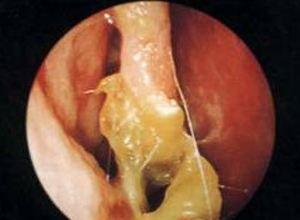

症状一:鼻粘膜溃疡、糜烂常见于鼻中隔前下区(Little区),多由慢性炎症引起。化学性气体、高温、干燥空气皆可成为诱因。此外,鼻中隔棘突或矩状突、鼻中隔穿孔、萎缩性鼻炎,也可引起局部鼻粘膜溃疡形成而导致出血。鼻窦的急性感染。

相关图片